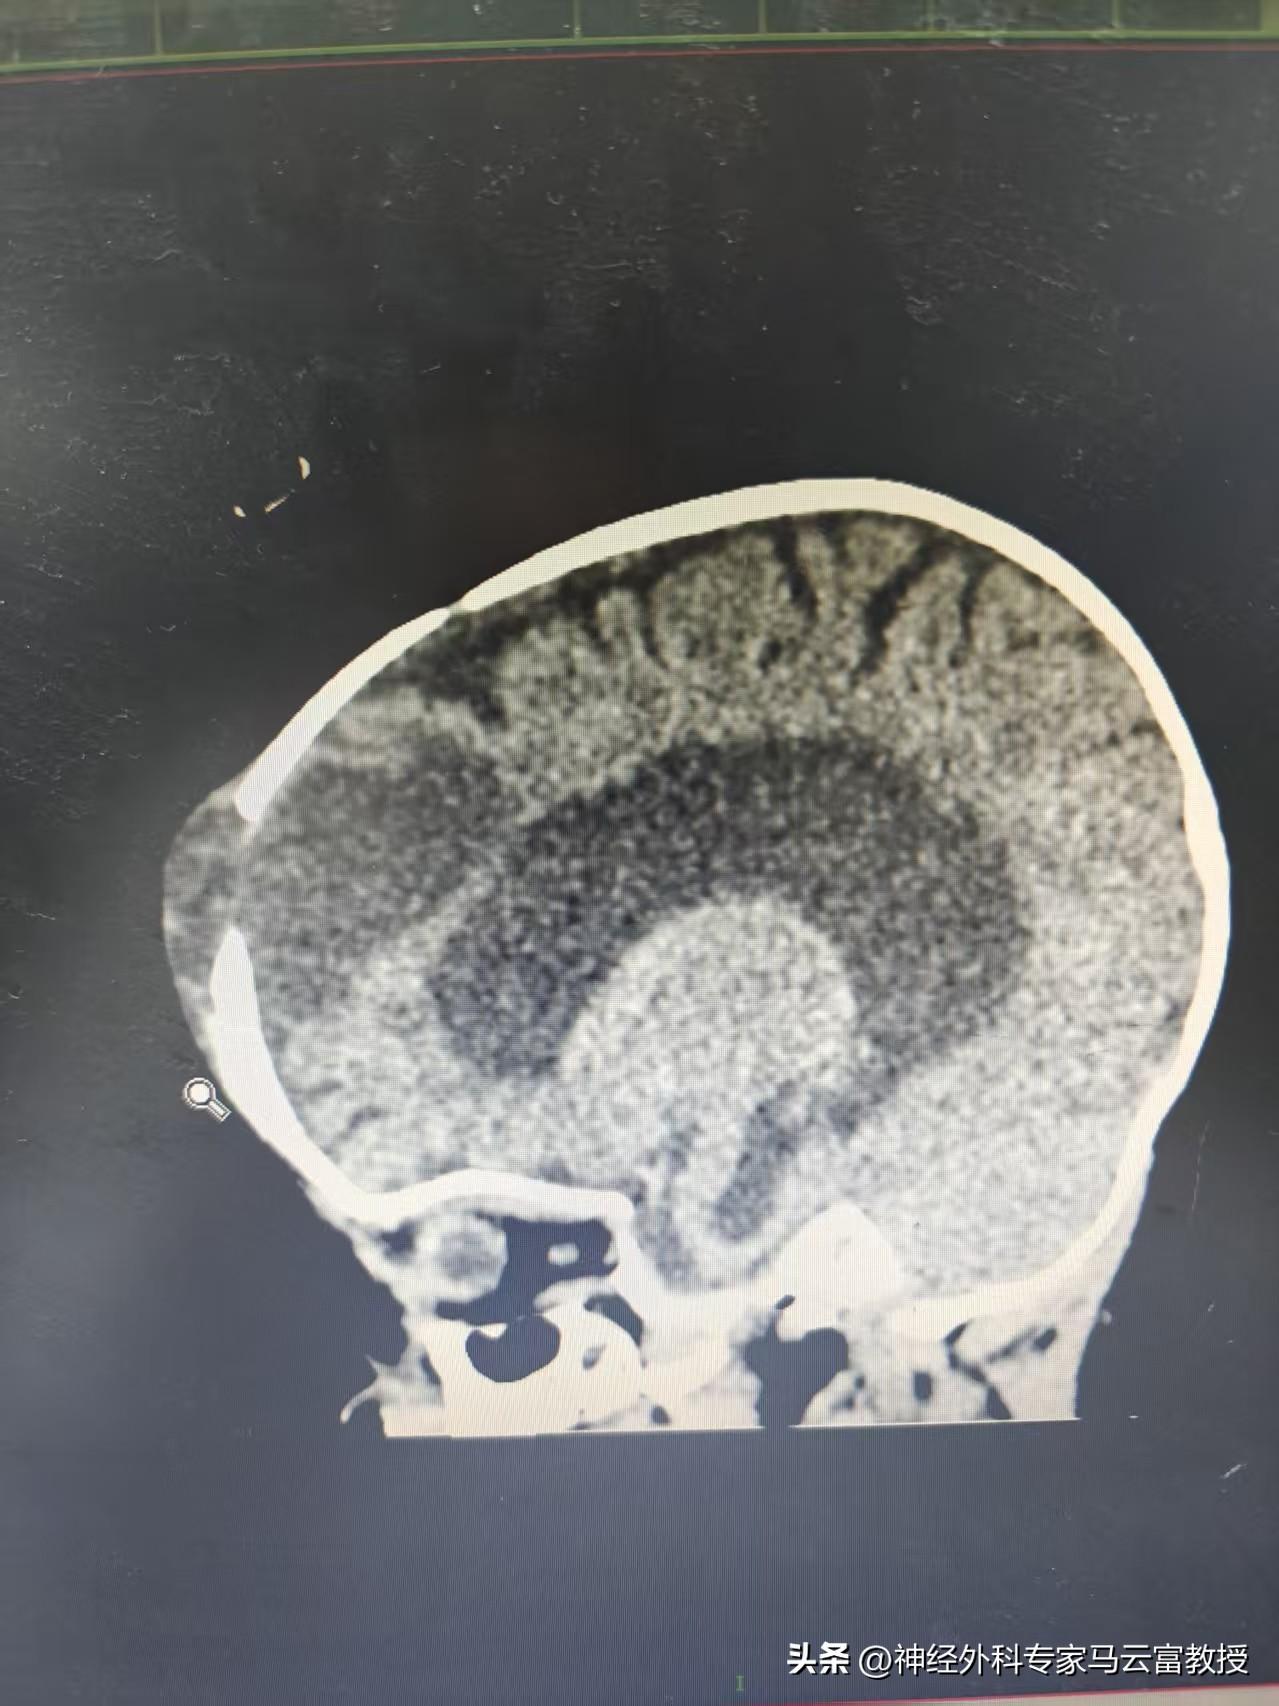

術前顱腦CT顯示右額部包塊和顱內相通

患兒入院後,科室給予了高度重視。馬雲富教授在詳細查看患兒並閱片後,憑藉其淵博的學識和數十年的臨牀經驗,敏銳地指出:CT顯示患兒右側額部存在顱骨及腦膜缺損,同時幕上腦室系統擴張。結合患兒曾有頭部外傷史,額部缺損可能與外傷有關,但當前問題的核心,是高度懷疑腦室內的積液正通過這處顱骨“缺口”滲透到顱外,從而形成了這個巨大的額部包塊——這就像是顱內壓力找到了一個意外的“泄壓閥”,將問題顯現於外。